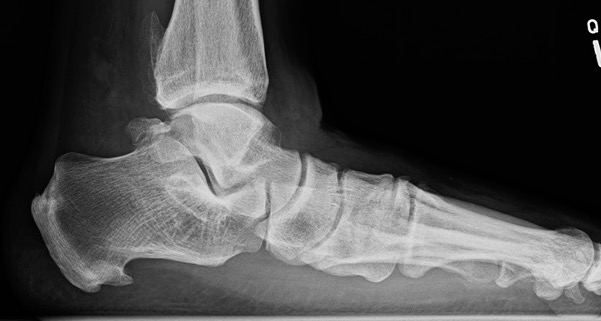

Lateral weight bearing

Early - reduced talo-metatarsal angle / Meary's angle

Late - subtalar joint OA